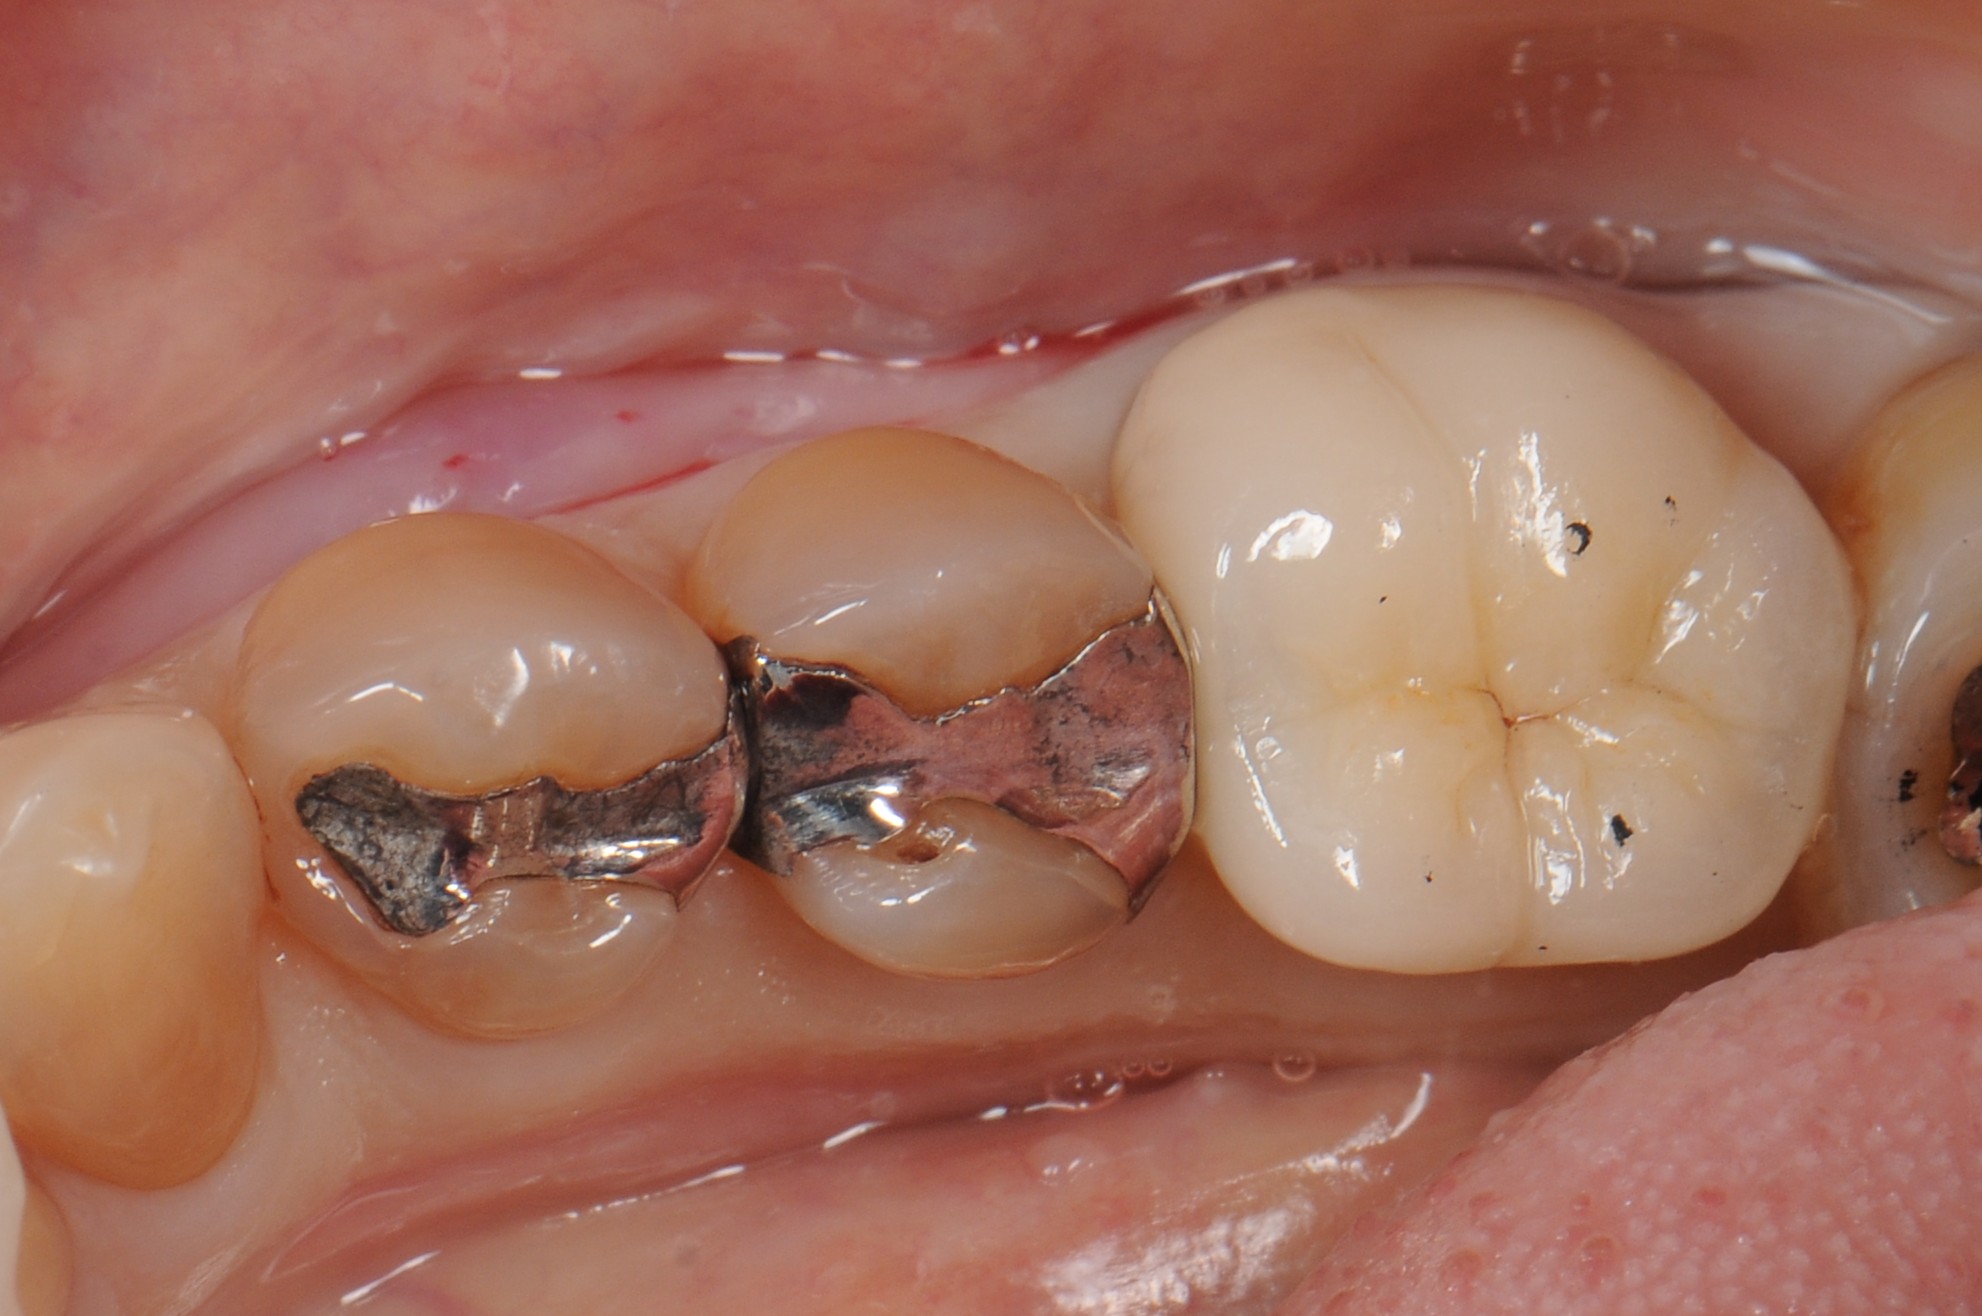

case8 症例(セラミックインレー・ダイレクトボンディング)

治療前

治療後

| 費用(税込み) | セラミックインレー:66,000円、ダイレクトボンディング:22,000円 |

|---|---|

| 治療回数 | 1歯につき3回 |

| 主訴 | 金属の修復物を白くししたい |